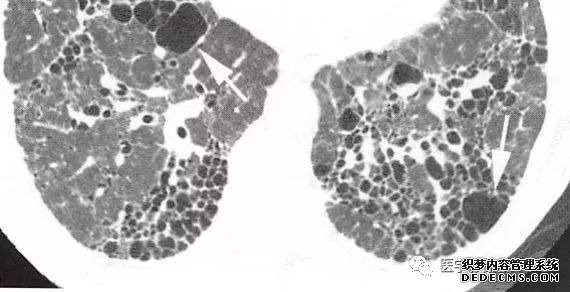

肺转移瘤的十种不典型CT表现